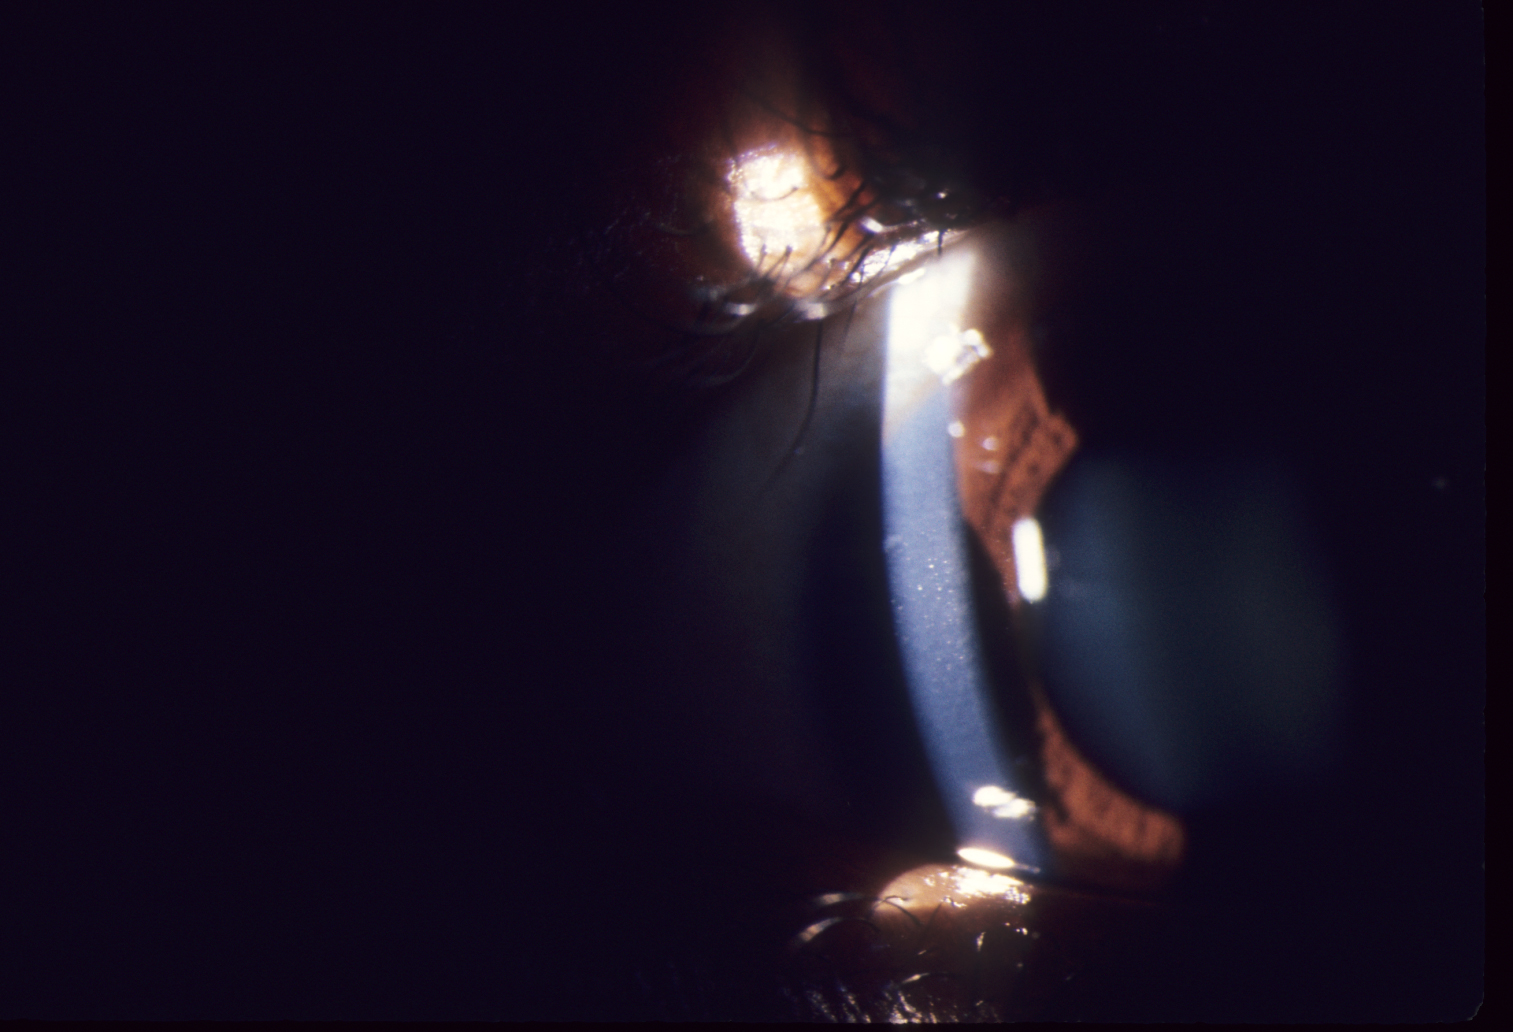

문자그대로 주근깨와 같은 작은 혼탁이 기질에만 존재하는 질환입니다.

작은 혼탁이 상피는 침범하지 않으며, 기질의 전층에 발생합니다.

미세한 회색 얼룩이 양측 각막의 전층에 발생하게되며,

비대칭적이며 종종 단안에만 발생하기도 합니다